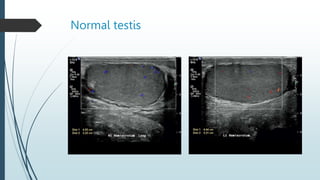

Ultrasound

The normal testes have a homogeneous,

moderately echogenic pattern.

 A testis is surrounded by a thin echogenic

fibrous band, which represents the visceral

component of the tunica vaginalis and the tunica

albuginea.

 In the absence of intrascrotal fluid, the tunica is

usually visualized only at its hilum as an

echogenic structure, where it invaginates into the

testis, to form the mediastinum testis.

Normal testis.

Normal testis